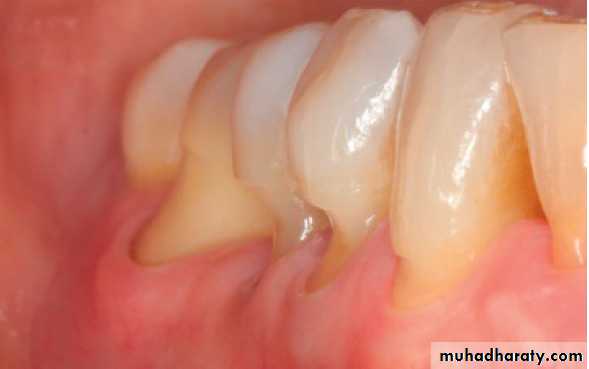

Furcation Involvement:

the pathologic resorption of interradicular bone within a furcation of a multirooted tooth due to periodontal disease. Classification:Ι, ΙΙ, ΙΙΙ, ΙV

• Special probe:

Nebers 2 , Za 3

Radiograph can detect 2 & 3

FI. Assessed all the entrances of possible periodontal lesion of multirooted teeth:

Buccal and /or lingual of mandibular molars.

Maxillary molar and premolars/ buccal /distopalatal/ mesiopalatal.

Due to furcation between MB and P:explored from palatal aspect.